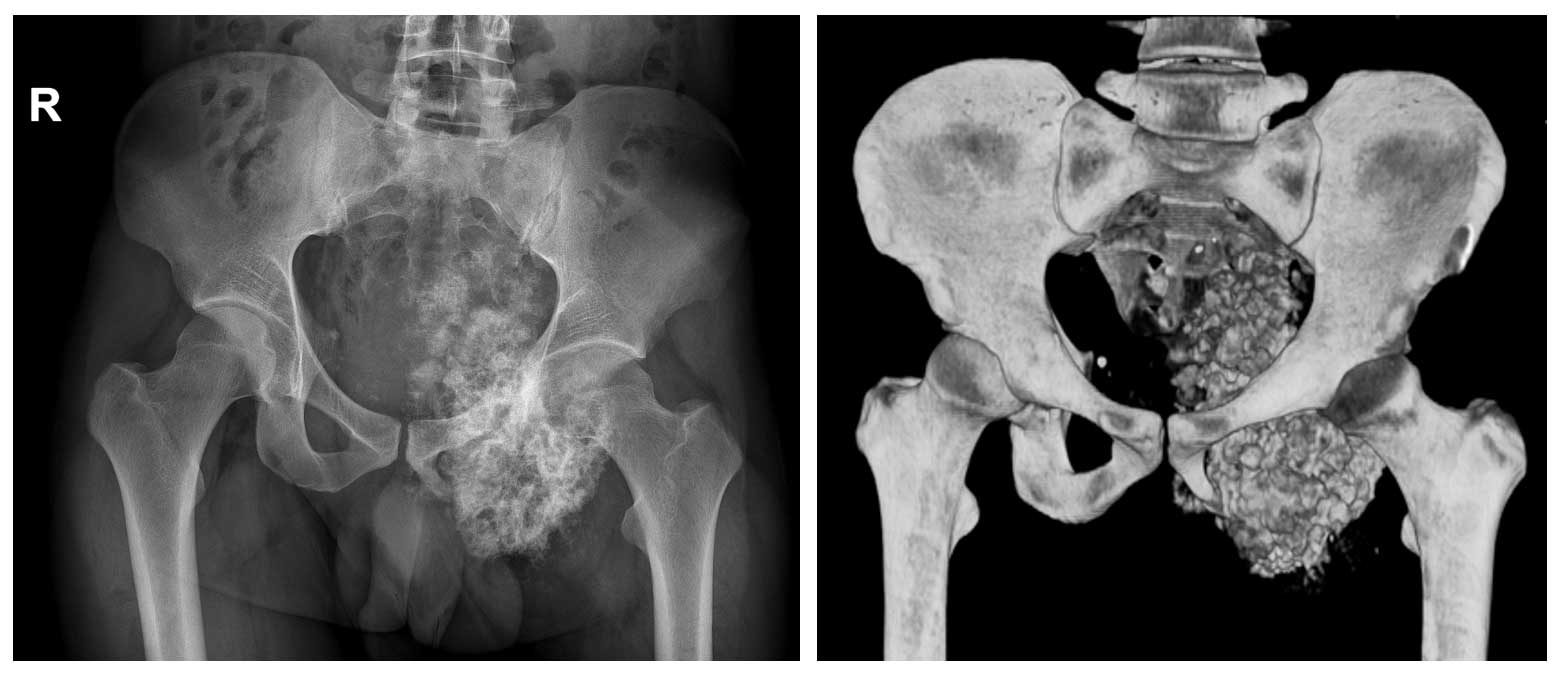

Ameliyat Öncesi: Röntgen ve 3BT’de sol asetabulum ve pubik kol kaynaklı obturator foromani ve hemipelvisi dolduran düzensiz sınırlı sklerotik tümör dokusu görülmekte.

Ameliyat Öncesi: Tomografide kemik yüzeyde harabiyete neden olan kalsifikasyon içeren düzensiz sınırlı kitle görüntüsü görülmekte.